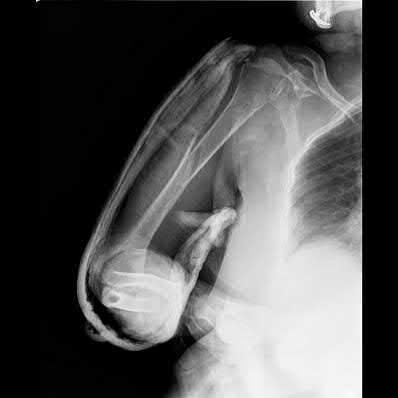

A 35-year-old-male sustains the fracture seen in Figure A. Which of the following reduction forces must be applied to the proximal fragment to correct the deformity commonly seen in these fractures?

Figure A demonstrates a displaced subtrochanteric femur fracture with an intact lesser trochanter. The pull of iliopsoas on the lesser trochanter as well as the intact external rotators and gluteal musculature results in the the proximal fragment being in a flexed and externally rotated or abducted position (the most common post operative deformity). Reduction manuevers must be biologically friendly but also counteract the flexion/abduction moment. Lundy's review article discusses evaluation and treatment of subtrochanteric fractures. The review article details the various implants often used which include 95 degrees plates, femoral reconstruction nails, or trochanteric femoral nails with interlocking options. Lundy's article discourages the use of the 135 degree screw and side plate combo due to high failure rates in these fracture patterns. Bedi et al also review treatment of these fractures and discuss common

problems of malunion, nonunion, and implant failure. The article reviews reduction techniques that are soft tissue friendly, as well as the use of appropriate implants in these fracture types.